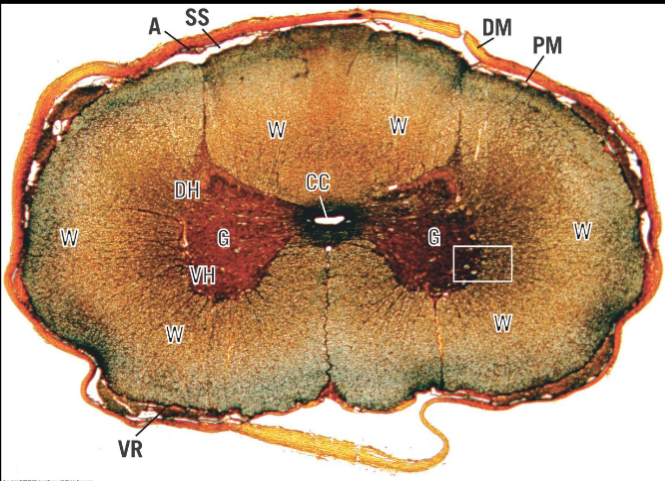

in the Spinal cord, where is the White matter located?

in the outer covering

in the Spinal cord, where is Grey matter located?

in the inner core

in the Spinal cord, what does its Grey matter contain?

somas of multipolar neurons & neuroglia nuclei

in the Spinal cord, what does its White matter contain?

collection of myenlinated axons w/ neuroglia nuclei